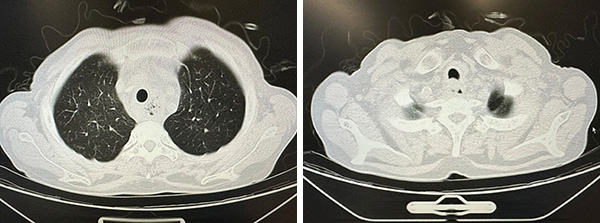

最终团队于气管镜直视下置入Y形金属覆膜支架,支架位置精准、释放完全。整个手术操作规范、流程顺畅,全程仅耗时半小时即顺利完成。“血氧饱和度上来了!95%、98%……稳定了!”术后即刻,手术室里传来振奋的通报声,W先生喘息症状显著缓解,呼吸困难改善,生命体征平稳,片刻转危为安。

Y形金属覆膜支架置入后

第二天复查CT,气管狭窄完全缓解,支架位置良好